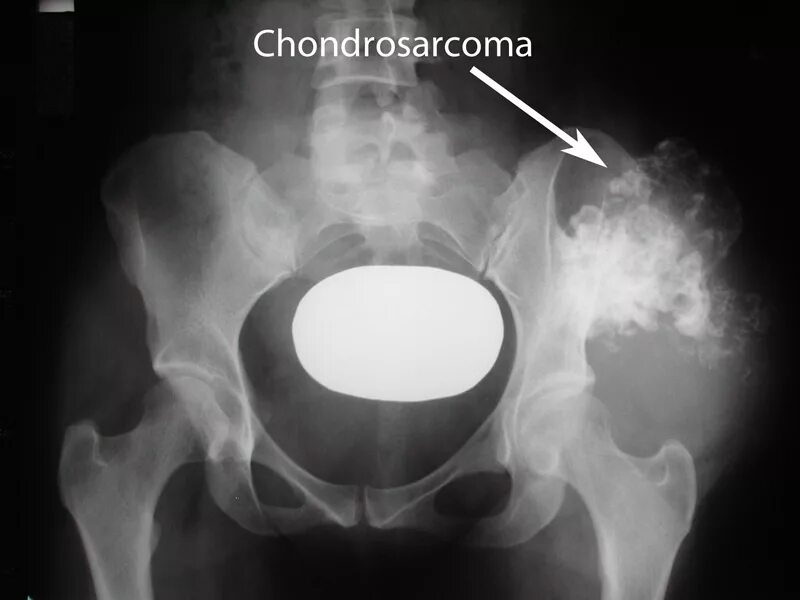

Симптомы рака костей у женщин после 50